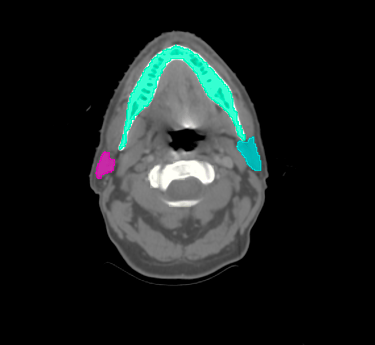

Head & Neck

Choose from a combined structure volume including BrainStem, Brain, Chaism, Mandible, Optic nerves Trachea and many more, or choose individual split sub-levels.